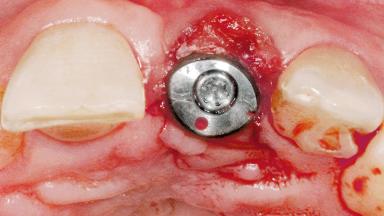

Late Flapless Placement of an Implant in a Maxillary Left Central Incisor Site

Anthony Sclar

A 39-year-old male patient presented with a chief complaint of discomfort and gingival discoloration around his maxillary left central incisor. He was in good general health and was a non-smoker. His past dental history was significant because of the traumatic fracture of tooth 21 in a sporting accident at age 13. Initial dental treatment included endodontic therapy and a full-coverage restoration. The patient became symptomatic 5 years later, when structural failure of the tooth resulted in the dislodgment of the crown. Endodontic retreatment, apical surgery, and post-and-core restoration were performed.